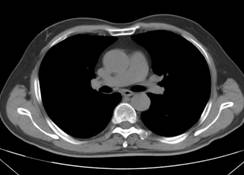

杨××,男,63岁,CT示右肺门占位(图1a~b)经穿刺活检证实右肺门部腺癌、纵膈淋巴结转移,基因检测提示“吉西他滨、5-Fu、铂类”化疗药物敏感;经三次介入治疗后CT(2012年12月19日)复查,瘤体明显缩小,纵膈肿大淋巴结消失(图2a~b);后无特殊治疗,4年后复查(2017年1月8日),病情稳定,瘤体不明显(图3a~b)。

图1a 图1b

图2a 图2b

图3a 图3b